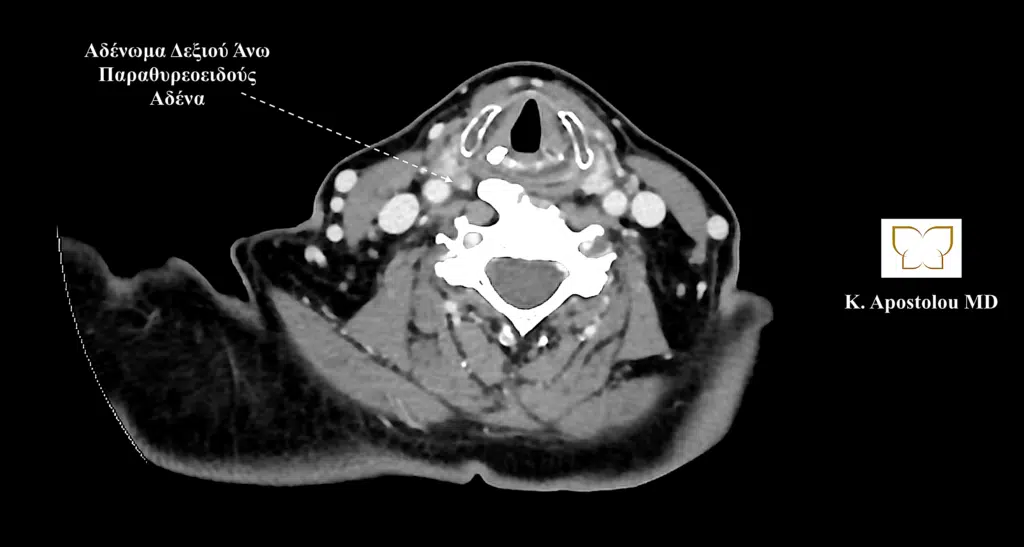

Ομοίως, η αξονική τομογραφία αποκάλυψε την παρουσία τριών αδενωμάτων παραθυρεοειδούς και πιο συγκεκριμένα του δεξιού άνω παραθυρεοειδούς, του αριστερού άνω παραθυρεοειδούς και του δεξιού κάτω παραθυρεοειδούς αδένα, καθώς και την παρουσία διόγκωσης του θυρεοειδούς αδένα με κατάδυση αυτού στο ανώτερο μεσοθωράκιο και την παρουσία πολλαπλών όζων θυρεοειδούς (καταδυόμενη πολυοζώδης βρογχοκήλη).

αδενωμα δεξιου ανω παραθυρεοειδους